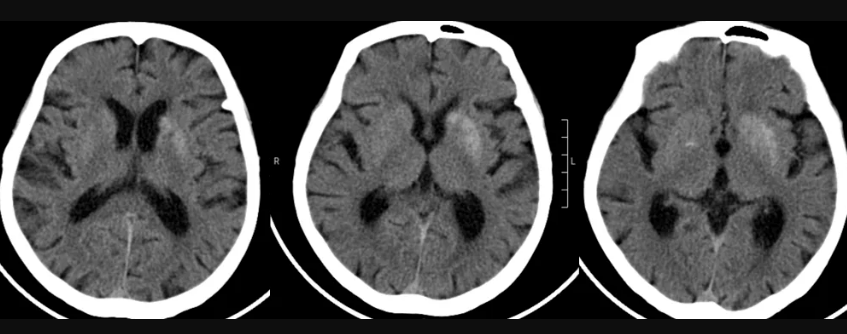

2)头部MRI和头颅MRA

MRI是脑组织的磁共振成像,是普通的脑部扫描,可以显示脑组织基本结构以及脑组织缺血和出血引起的改变;MRA是脑血管磁共振成像,是用磁共振扫描脑部血管,可以判断脑血管是否存在血栓、出血、狭窄,并能确定血管狭窄与闭塞的准确部位。